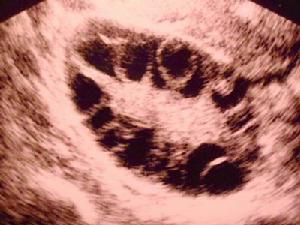

2.除病史外,還需參考體檢和婦科檢查,激素水平檢測和超聲、CT檢查等。盆腔包塊在雙合診時由於盆腔有緻密粘連往往不易查出,而作三合診查出率較高,常可捫及於增厚的骶、主韌帶處有小結節或盆腔包塊。B超查出包塊有助於診斷和盆腔探查術前定位。B超圖像為邊界清晰的盆腔腫塊回聲,有少量液體圍繞。

2.B超檢查 可見包塊並有少量液體圍繞。